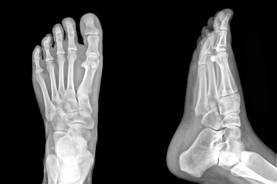

PAINFUL OR UNSIGHTLY BUNIONS?

At the Red Deer Foot Institute, our Doctors are trained to specifically treat problems associated with your feet or ankles. Below are several of the most common problems that we see on a day to day basis: